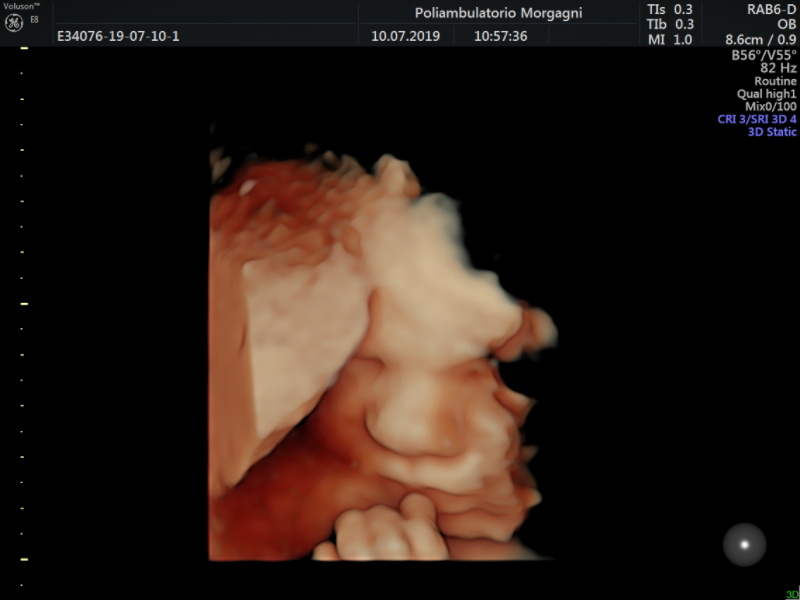

Nel caso che il tesoro, nelle ecografie precedenti, sia risultato un po’ sovrappeso o un po’ sottopeso, sarebbe meglio eseguire una ulteriore valutazione della crescita fetale e del benessere fetale fra la fine dell’ottavo o l’inizio del nono mese.